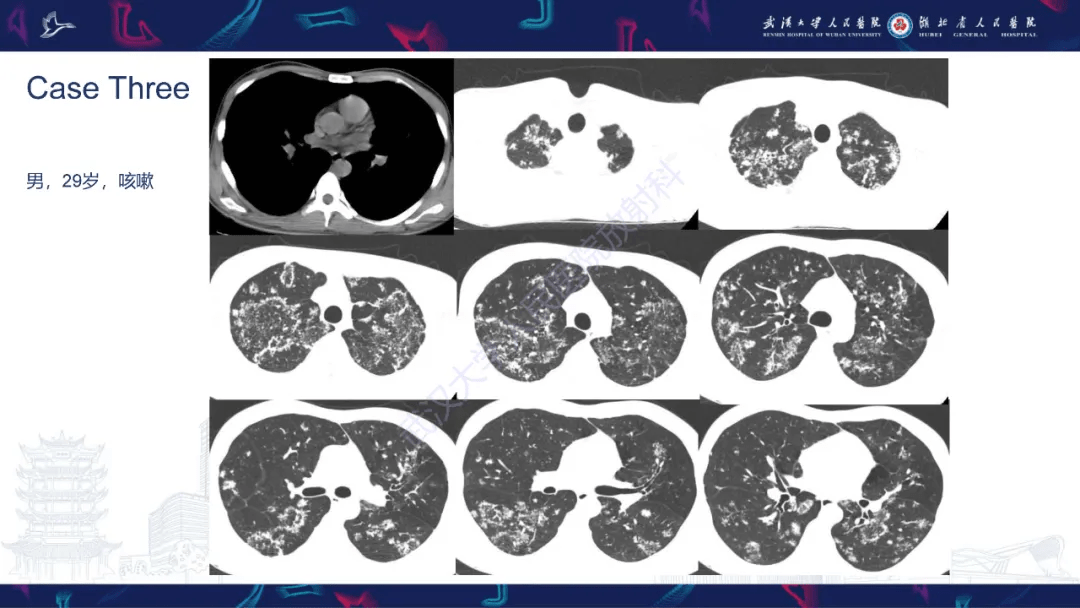

双肺大片的活动性结核病灶.

这个胸部ct是活动性结核吗